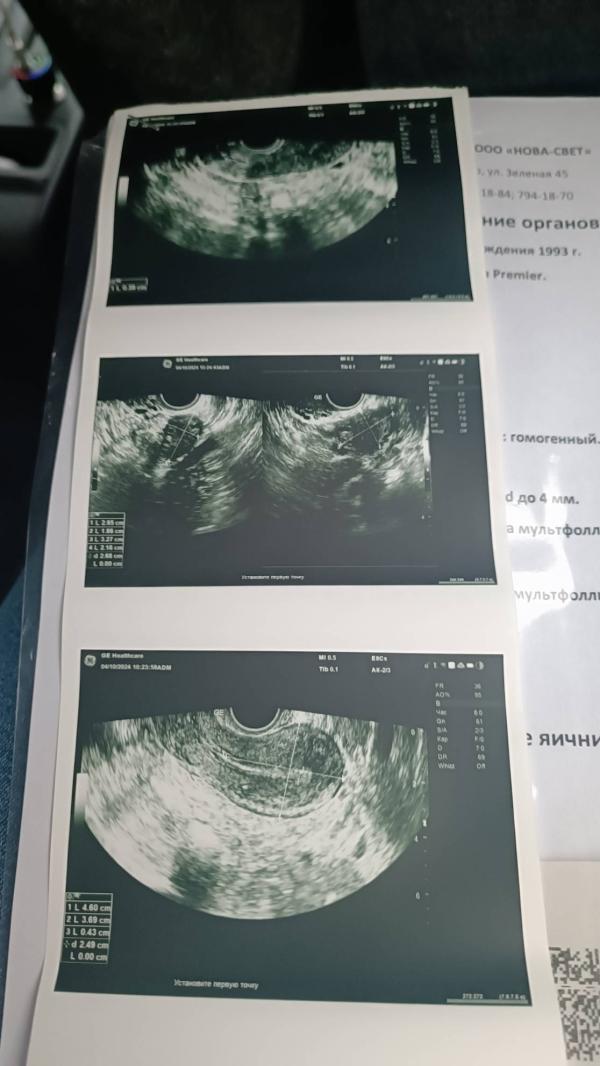

В пятницу на УЗИ всё чисто, эндометрий тонкий, как только закончились месячные.